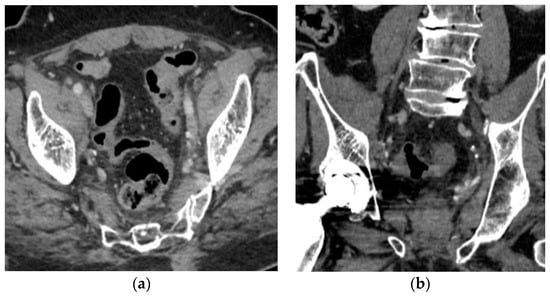

2. Case Report